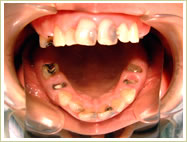

●すべての歯を失った場合

79歳 男性 インプラント埋入数:12本 画像拡大

治療前

治療中